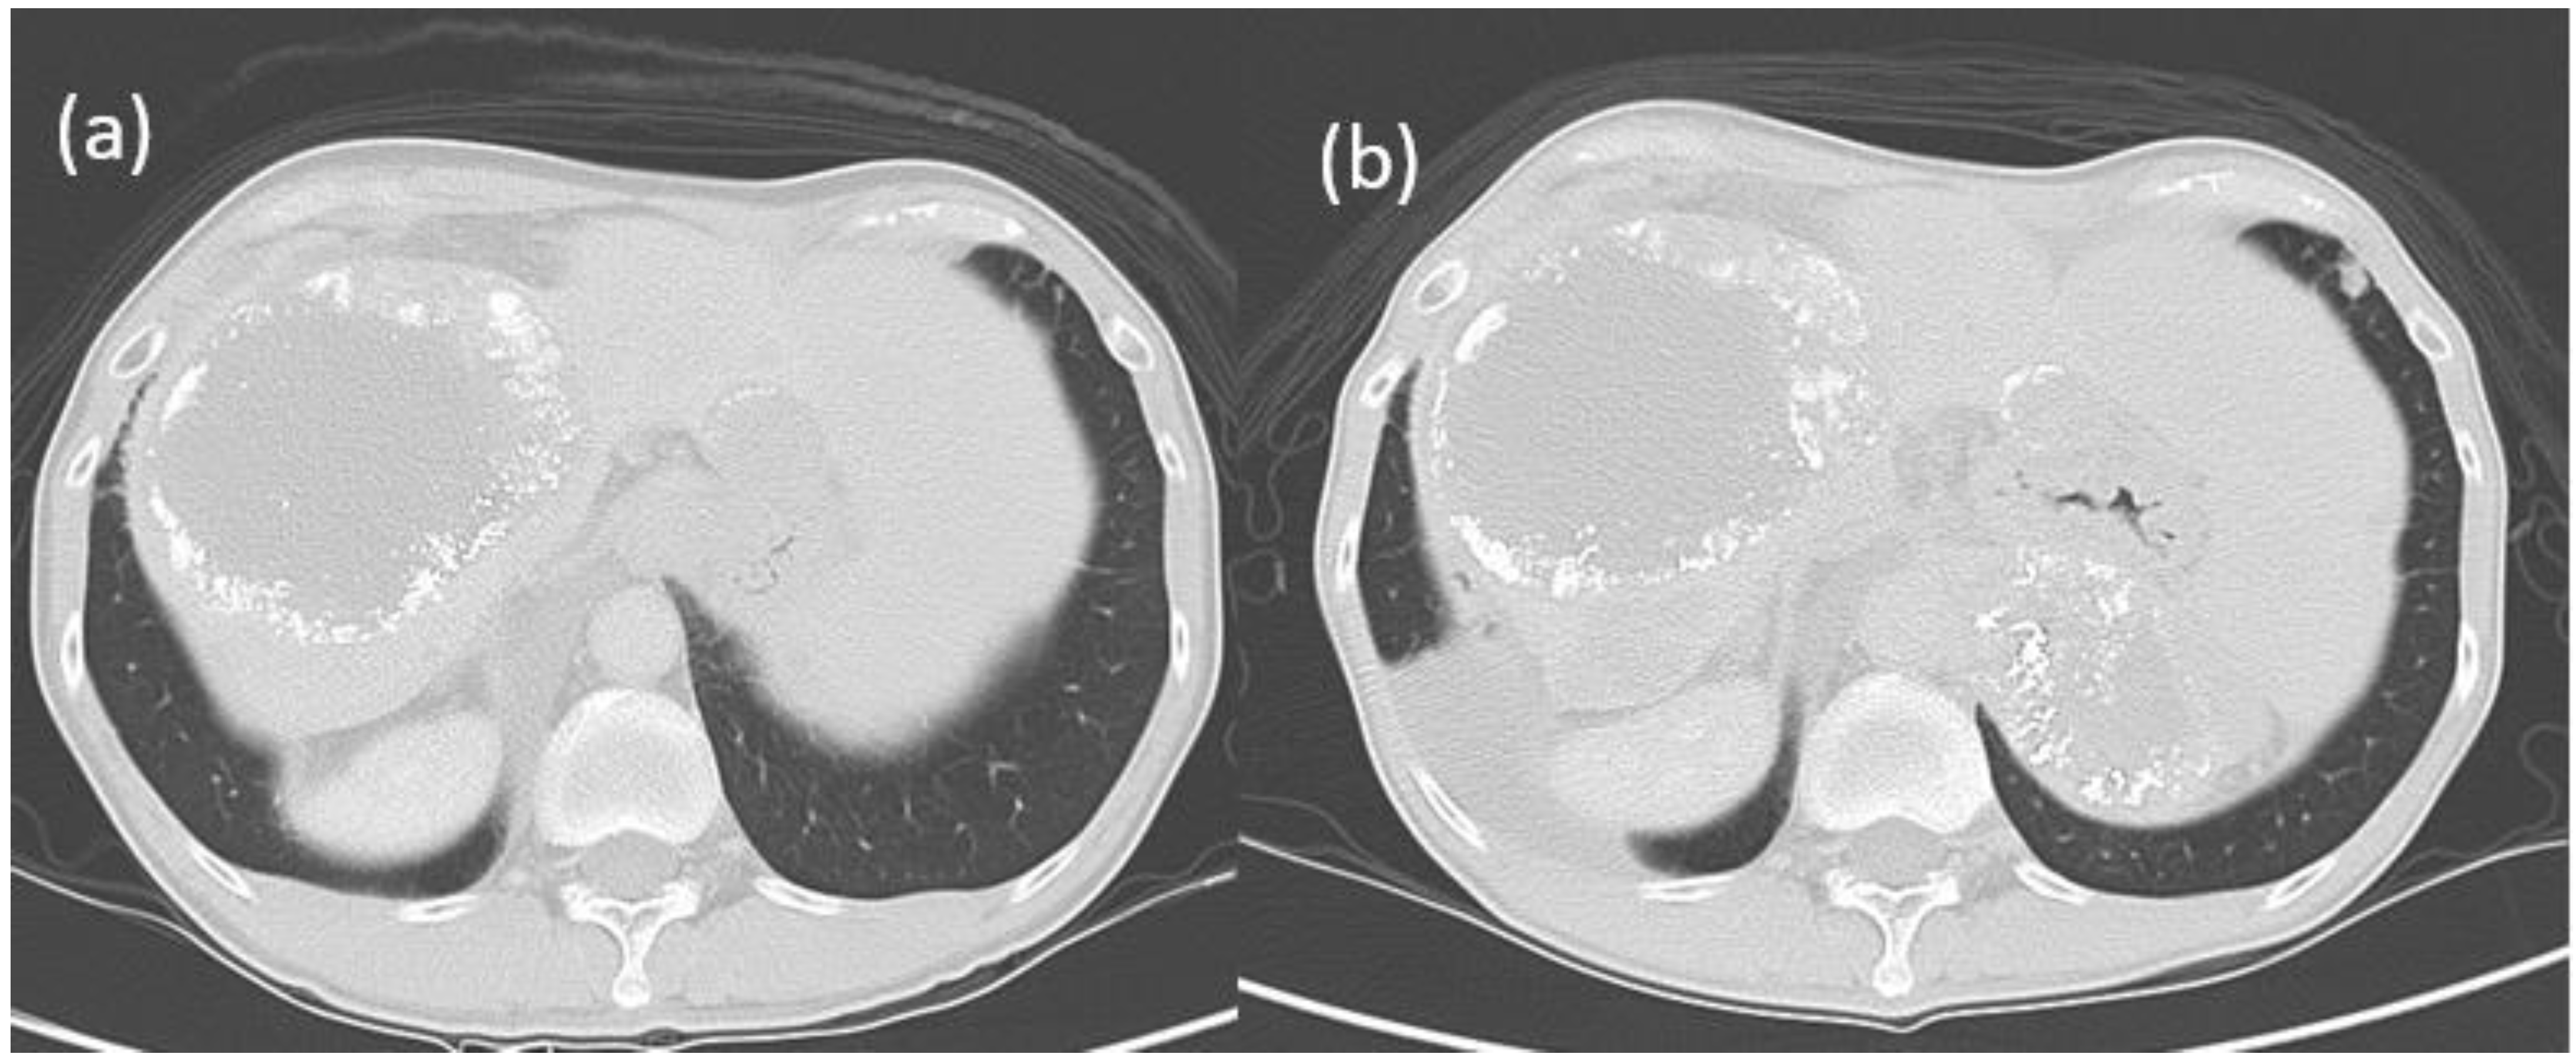

However, a bronchoscopic biopsy showed tumor cells with necrosis. Repeated bronchoscopy three weeks later showed the tumor covered with necrotic material at the orifice of the RML and protruding into the distal part of the truncus intermedius (Figure 1). Bronchial brushing cytology showed the same findings as the previous one. The bronchoscopic biopsy showed carcinoma cells with canalicular pattern and necrosis. IHC studies (Table 1) were negative for hepatocyte paraffin 1 (Hep Par-1), AFP, glypican 3, cytokeratin (CK) 7, CK 20, and thyroid transcription factor 1 (TTF-1) but equivocally positive for p40 antibody, p63 and polyclonal carcinoembryonic antigen (CEA) and CD 10 rare and equivocal. His serum CEA titer was 4.0 ng/mL (normal < 5.0 ng/mL). The lung tumor reduced markedly in two months after sorafenib and local radiation therapy but rebounded three months later with no further continuation of the treatment. The patient developed subsequently many large nodules varying from 2 cm to 4 cm in both lungs and massive right pleural effusion. The pleural fluid CEA titer was 2.1 ng/mL with negative results for cytology and cell block. Follow-up abdominal tomography 6 months later showed no increase of the liver tumors (Figure 3a); however, the follow-up abdominal tomography two years and one month after the bronchoscopy showed several new viable HCCs in the lateral segment (Figure 3b) and a persistent truncated right portal vein, probably due to tumor compression or thrombosis. Finally, he died of massive gastrointestinal bleeding 49 months after initial diagnosis. His serum AFP had been steadily rising up to 18,350 ng/mL over the past 4 years.

Figure 3. Abdominal tomography of Patient 1 (a) six months after bronchoscopy (b) two years and one month later showing two new liver tumors and a new, small nodule in the anterior aspect of the left lower lung.